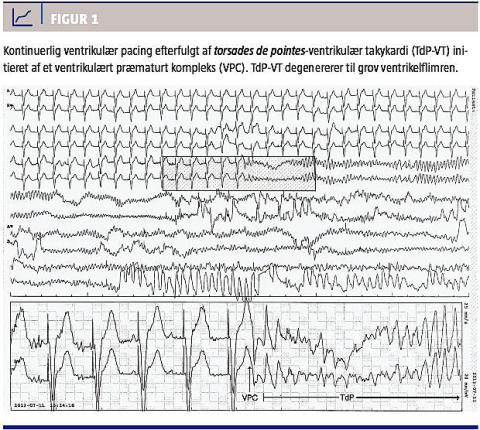

Atten timer efter pacemakerimplantationen fik patienten pludselig hjertestop. Ekg-monitorering (Figur 1) viste kontinuerlig ventrikelpacing efterfulgt af et ventrikulært præmaturkompleks svarende til en T-tak. Dette initierede en polymorf ventrikulær takykardi (VT) med alternerende elektrisk akse og varierende amplitude, hvilket er foreneligt med torsades

de pointes

-VT (TdP-VT). Efterfølgende sås grov ventrikelflimren (VF). Patienten fik øjeblikkelig hjerte-lunge-redning og blev defibrilleret én gang, hvilket resulterede i fornyet ventrikulær pacing med underliggende tredjegrads AV-blok og spontan cirkulation.